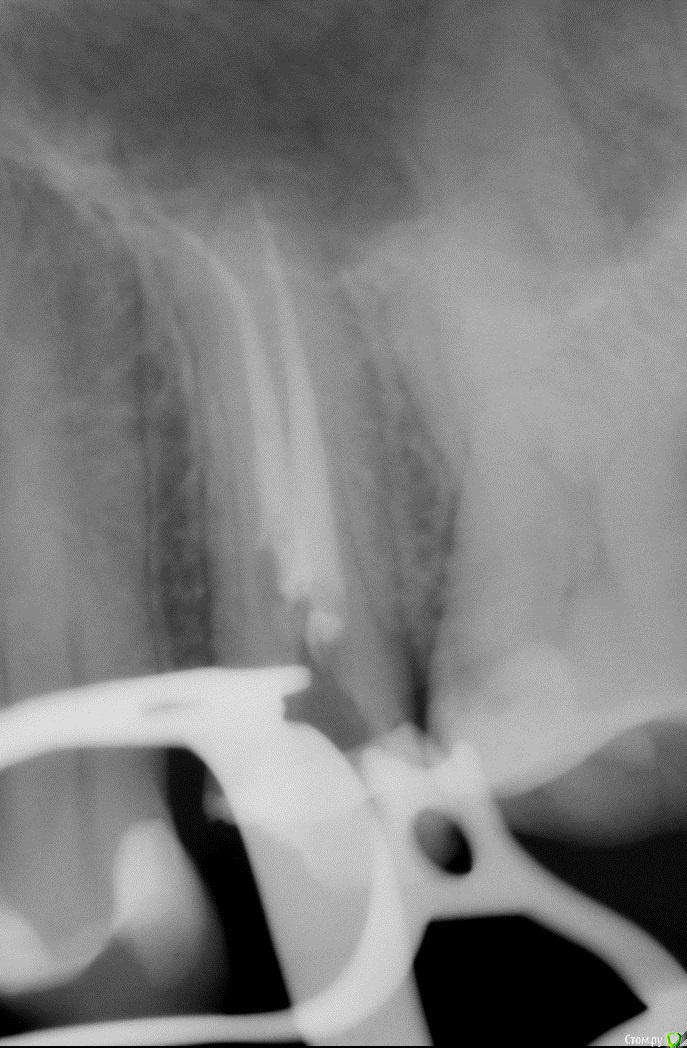

25 зуб был депульпирован и запломбирован в 2004 году. В 2015 году разрушился и был восстановлен с помощью 2 титановых штифтов. После чего начал болеть. Боль прошла осенью 2017го. В январе 2018 повезло попасть к хорошему эндодонтисту, коим была выявлена причина старой боли, и каналы были перелечены под микроскопом. Боли не было, и через 2 недели я отправилась устанавливать вкладку и коронку. Через 3 дня после распломбировки каналов под вкладку и снятия слепков зуб заболел. Зуб ноет и немеет 5ый день. Тенденции на спад или усиление нет. Обратилась к эндодонтисту, вскрытие каналов показало что трещин и перелома корня нет, каналы не повреждены, крови нет. Решили ждать неделю и смотреть что будет с болью. В квалификации энодонтиста сомнений нет.

Снимки после перелечивания каналов и после распломбировки под вкладку прилагаю.